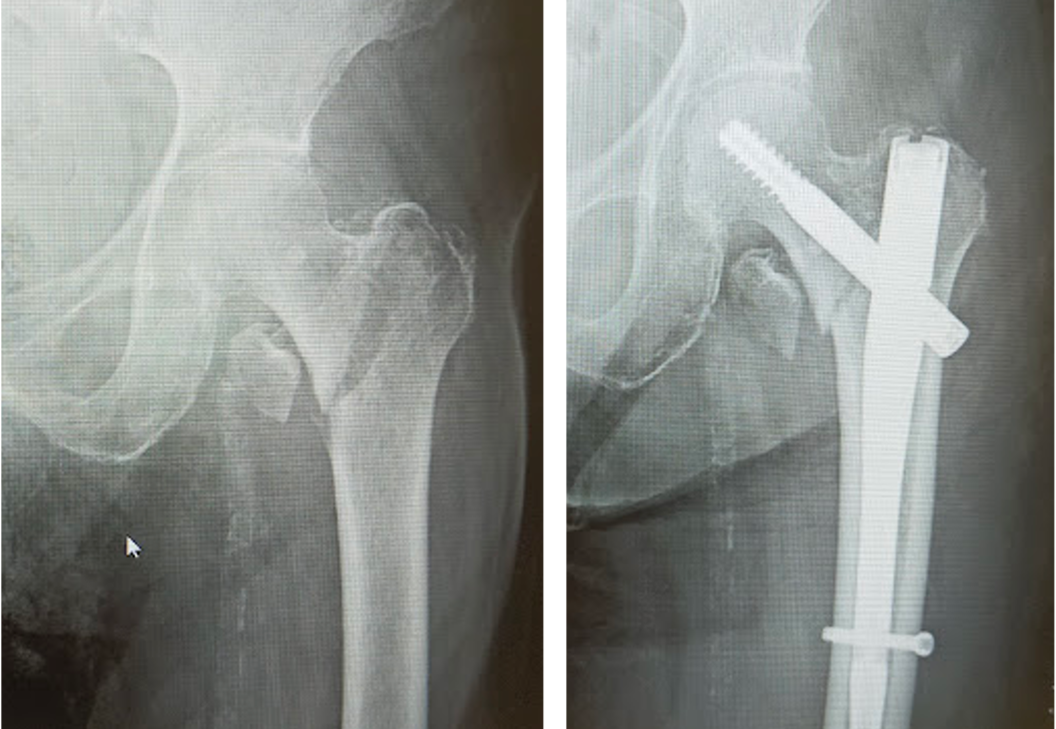

大腿骨近位部骨折は骨粗鬆症が基礎にある高齢者に非常に多い骨折です。寝たきりになりやすく、また生命予後にも関わるため、早期の手術が望ましい骨折です。

大腿骨転子部骨折に対する骨接合術